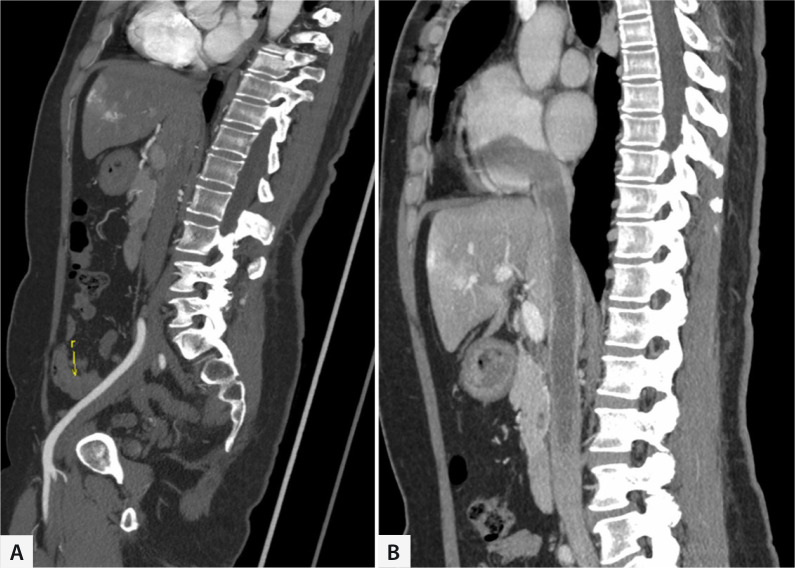

Introduction: Intracardiac leiomyomatosis is a rare, histologically benign, but biologically aggressive tumor developed from uterus. This study aimed to summarize our experience with one-stage surgery for intracardiac leiomyomatosis.

Methods: We retrospectively reviewed seven patients who underwent surgical treatment for intracardiac leiomyomatosis between May 2016 and November 2021.

Results: All seven patients were female, aged 35 to 57 years. All lesions in the veins and cardiac chambers were removed entirely. Four of the seven patients received tumor thrombectomy through an abdominal approach. The other three patients received median sternotomy and cardiopulmonary bypass. No perioperative deaths or serious complications occurred during the observation period. The mean operation time in the abdominal approach group was shorter than that in the cardiopulmonary bypass group (308.9 ± 93.2 minutes vs. 486.3 ± 108.6 minutes; P=0.031). Blood loss during surgery in the abdominal approach group was less than that in the cardiopulmonary bypass group (1625 ± 216 mL vs. 2500 ± 1080 mL; P=0.148). All seven patients were free from tumor recurrence or death during the follow-up.

Conclusion: For patients with intracardiac intravenous leiomyomatosis single-stage operation through an abdominal approach under the surveillance of intraoperative transesophageal echocardiography without the need for cardiopulmonary bypass for specified patients is feasible. Patients in the abdominal approach group can benefit from a shorter operation time and less blood loss. In our small series of varied presentations and tumor extent, we have been able to avoid two-stage surgery, because even short-term interval between the two operations may result in recurrence.